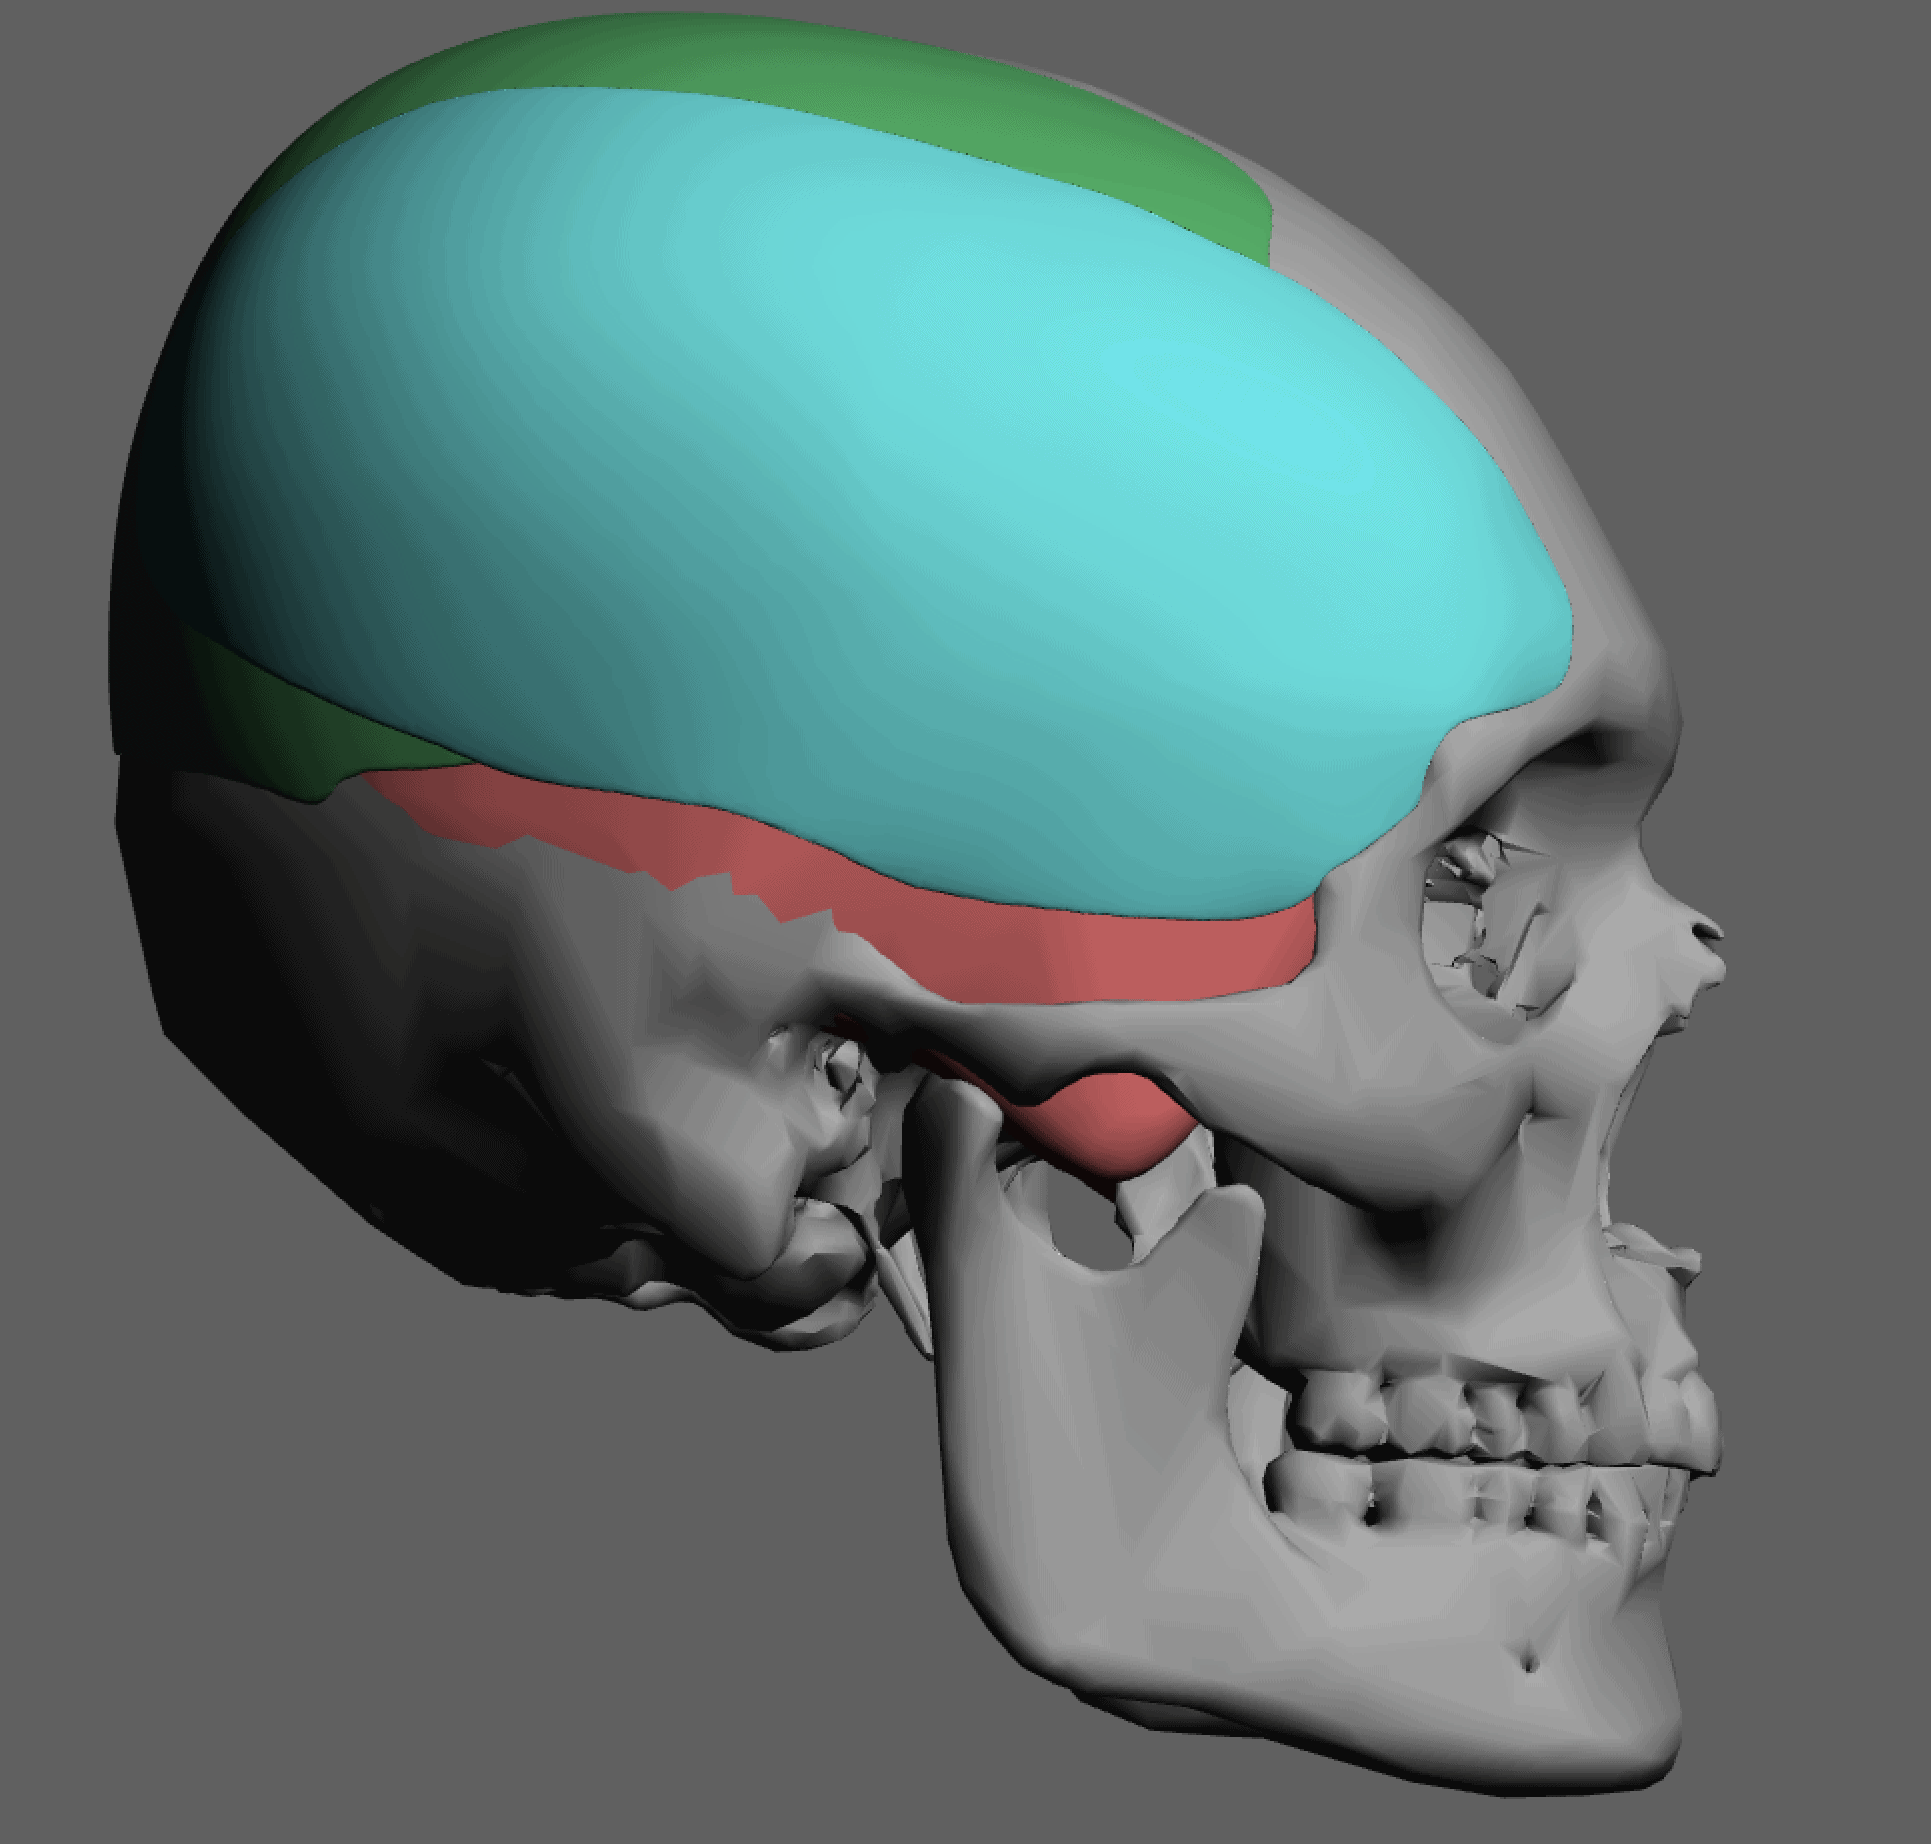

Desire for head shape asymmetry improvement as the final stage of total skull reshaping surgeries. (previous skull implants are in green color)

Placement of custom temporal implant through an incision behind the ear.

Desire for head shape asymmetry improvement as the final stage of total skull reshaping surgeries. (previous skull implants are in green color)

Placement of custom temporal implant through an incision behind the ear.